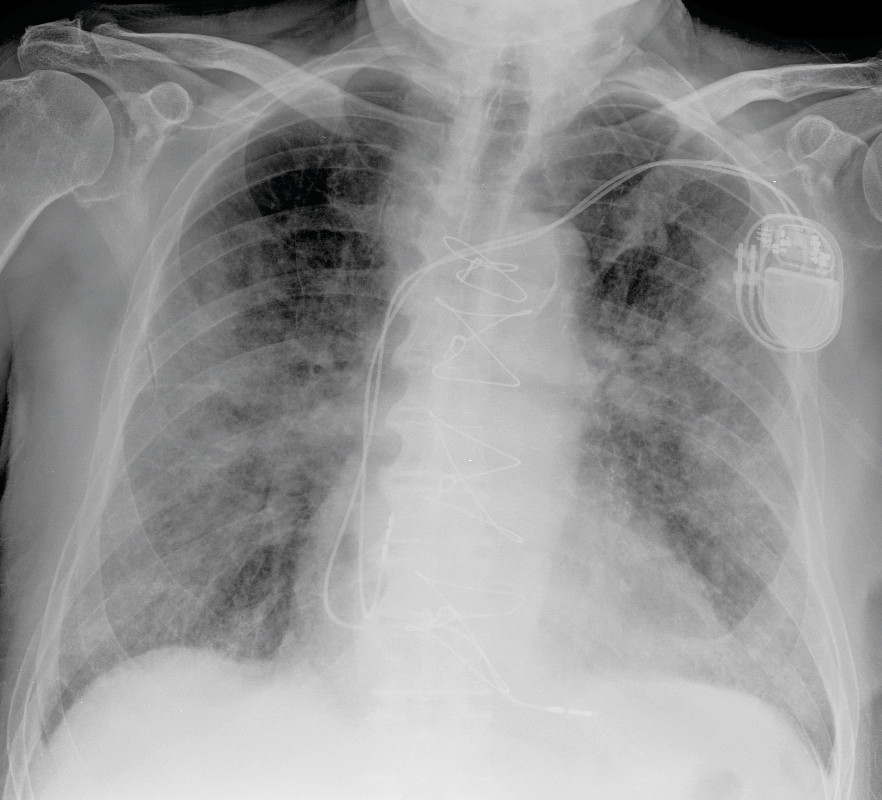

His GP had known the patient for many years. He had existing hypertension, three-vessel disease and had suffered inferior wall infarction. He had GOLD Stage 2 chronic obstructive pulmonary disease and benign prostatic hyperplasia. Because of a second-degree AV block type II with left bundle branch block, he had had a bicameral pacemaker implanted nine months before the incident in question.

Chest X-rays showed no convincing signs of congestion, but increasing patchy opacities with increasing consolidation which indicated disease progression (Fig. 2). In the course of the evening on day 7 his breathing became steadily more laboured, with a respiratory rate of over 40 per minute and oxygen saturation down towards 60 % despite a high oxygen supply by mask with reservoir bag.

While the first X-ray image of the lungs on day 2 showed no opacities, the patient had ground-glass opacities in all sections of the lungs on the pulmonary CT angiogram performed on day 5. Ground-glass opacities can be seen with several conditions and a characteristic feature is that the changes do not obscure the lung structures. Such opacities, with or without consolidation, are described in patients with COVID-19 (11–14). With consolidation, the normal anatomy of the lung is obscured by the opacities. CT must not be used as a diagnostic or screening tool, but may be relevant in cases where there is suspicion of complications that have not been clarified by chest X-ray (15). CT may be more sensitive than rRT-PCR in early stages of the disease and in an epidemic area, but is non-specific, and other interstitial pneumonias may yield similar findings (16–17). For these patients, CT will be a very limited resource, because time-consuming disinfection of the laboratory has to be done after each examination. No new CT was taken during the course of our patient's illness, but on day 7 a chest X-ray was taken that showed patchy opacities with increasing consolidation (Fig. 2). This indicated disease progression.